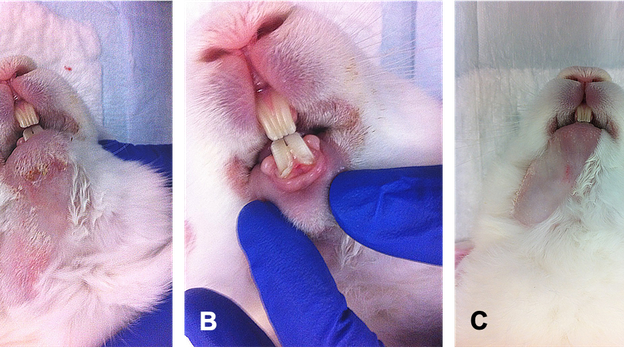

Outcome of a rabbit model for late irradiation effects in mandibular oral mucosa and bone: a pilot study

Angiopathology

Experimental model

Microcirculation

Radiology and radiotherapy

SDF imaging